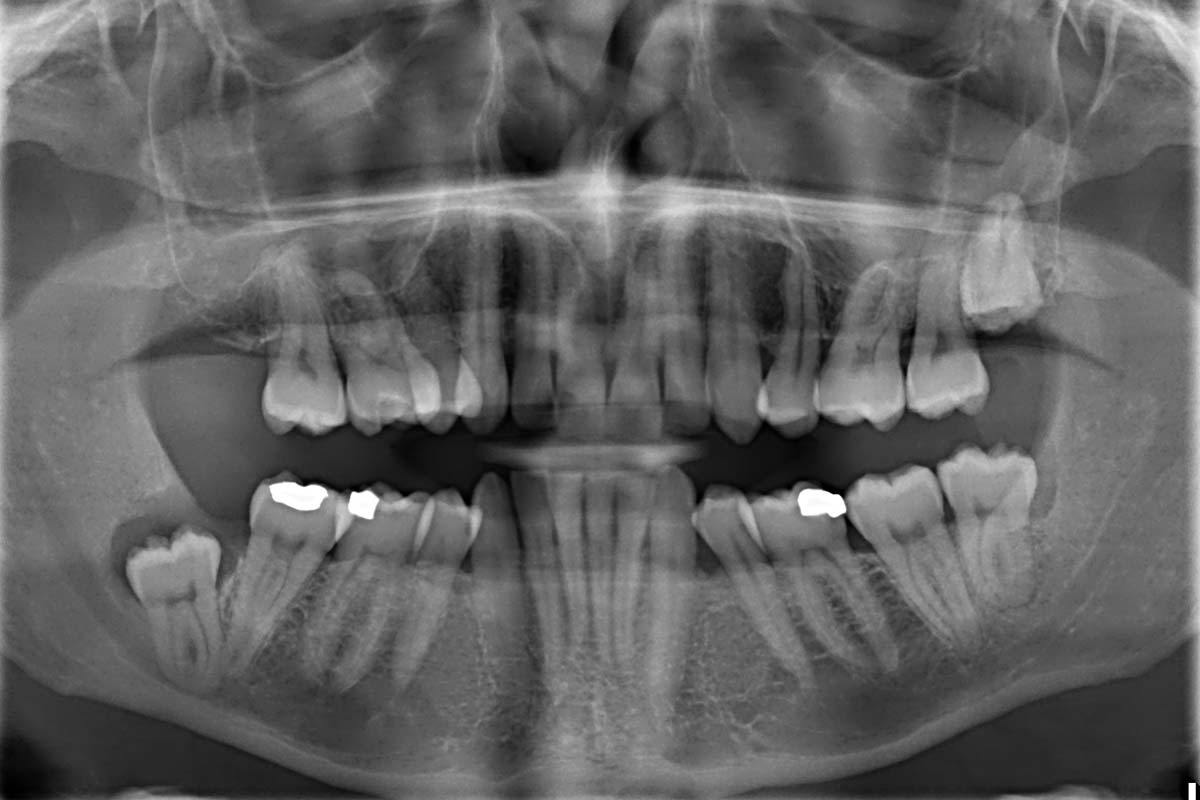

Most people have a standard X-ray when they first register with their dentist so that he/she can do a thorough check. Thereafter, it is typically only needed every few years, although this might be more frequent if you have gum or tooth problems.X-rays are an important way for your dentist to ensure your mouth is in good condition and prevent major issues occurring further down the road. Benefits include being able to spot hidden abscesses, tooth decay lurking beneath fillings, bone loss caused by gum disease and generally highlighting anything amiss that cannot be seen by an oral examination so it can be nipped in the bud.Dental X-rays are also important at intervals for children – the British Dental Health Foundation officially recommends them when a child’s second teeth are coming through. This enables your dentist to check whether the baby teeth are coming out at the right pace to allow for permanent teeth, and find out whether there is enough space for incoming teeth to grow properly.When it comes to dental X-rays while pregnant, The British Dental Association confirms the procedure is safe – no harm will come to your baby.